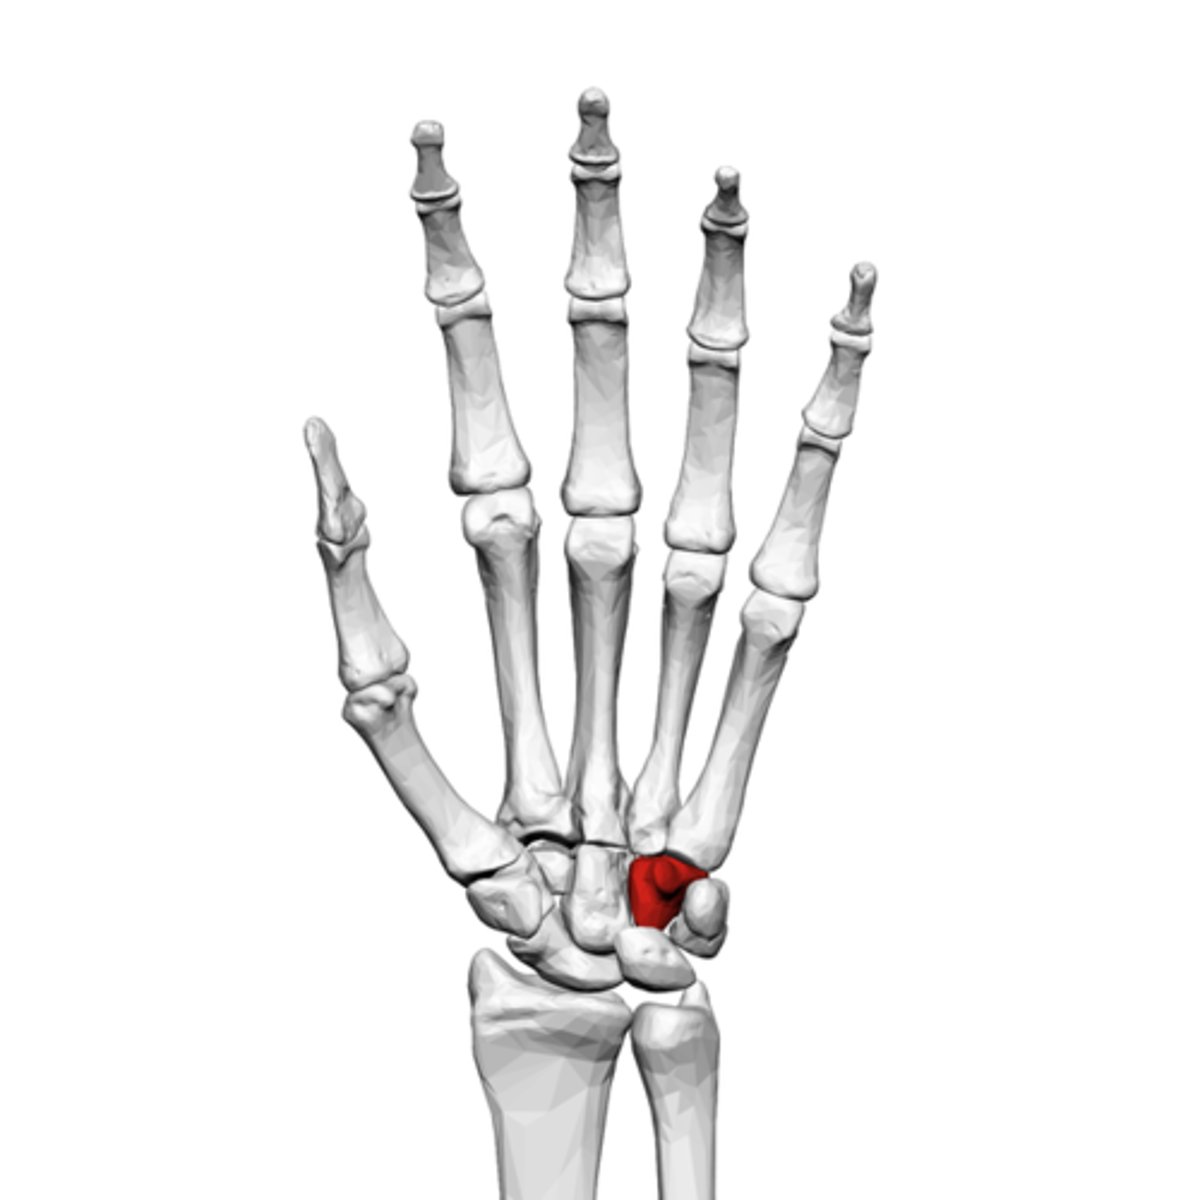

What is the term of the bones highlighted in red?

Hamate